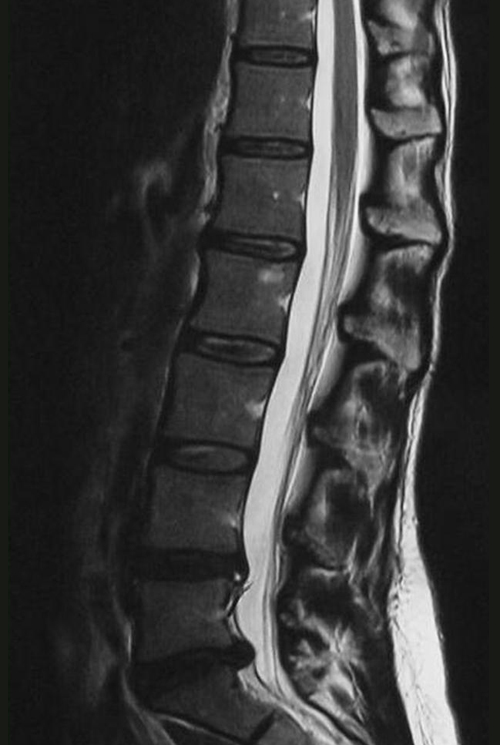

A free medical education seminar series for everyoneA FREE spine education seminar series for everyone Back pain has many faces and to many people it can be distressing, disabling or even frightening. Whether back pain comes from a strain, degenerative disc disease, a herniated disc, spinal stenosis, spondylolisthesis, a complex deformity or even a fracture, there are many options that can help you to live an active lifestyle. Additionally, osteoporosis is another disease that you may not even know you have. Learn from these dynamic experts about the various types of back problems and the latest treatments available. We will discuss the problems, the solutions and leave time for your questions to help you be active. Talk with the experts and get your concerns addressed. Spine Program